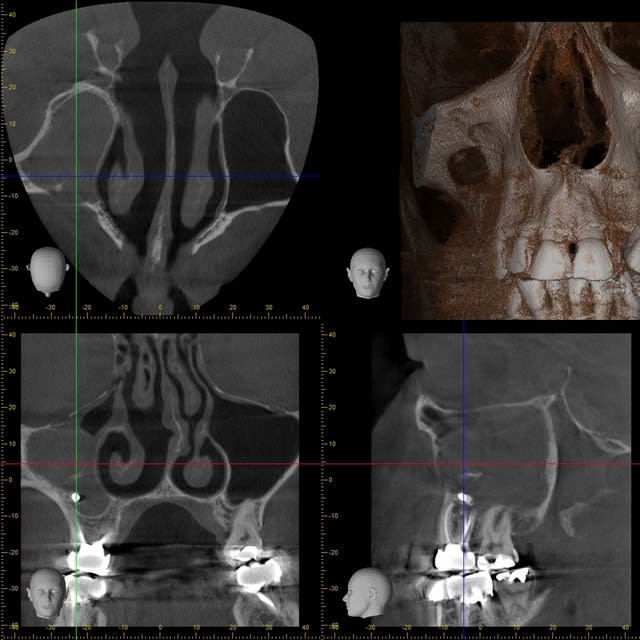

Que pensez-vous de cette bouse très radio-opaque dans le sinus maxillaire gauche ?

Pâte à canaux (un pot entier) ?

Noyau de pêche ?

Boulette de shit ?

Comblement de sinus au MTA par voie endocanalaire !

Vu la quantité, on comprends qu'il a les moyens ton patient !